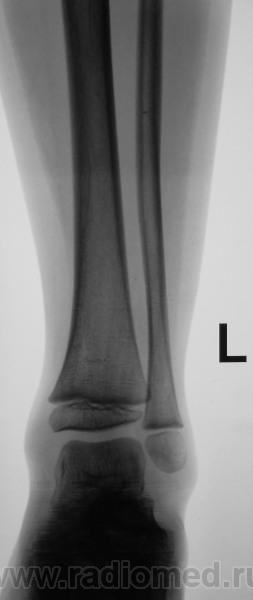

Ребенок из коммерческого областного ЛПУ был направлен по месту жительства, чтобы "доснять" остальные суставы. Выставлен диагноз ревматического полиартрита

Да нет. Правый локтевой какой-то "неискренний".

По мне так явные - деформация и суставной впадины и локтевого отростка. Природу не скажу. Тут приоритет за лабораторными данными.

И + склероз субхондральный.

И фрагментация локтевого отростка.

Точно НЕ ревматический процесс: "...Суставной хрящ в процесс не вовлекается, поэтому деформация суставов при ревматизме не происходит."

Конечно спокойно, спокойно везде, кроме правого локтевого сустава...

Дите же, артроз рано еще))) Да и признаков нету, остеофитов нету, щель не сужена, какой-то видимой перестройки костной ткани нету. При скудном анамнезе больше ничего не придумывается. Плюс есть фрагмент локтевого отростка, мог ребенок упасть или стукнутся об что-то.

Валентин Львович, думаю, вероятнее всего, это, все таки, ревматоидный артрит (и так бы и написал в протоколе, пусть утверждают обратное). Но такого ни разу не видел, поэтому с уверенностью утверждать не могу. Термин "вторичный" артрит для меня загадка.